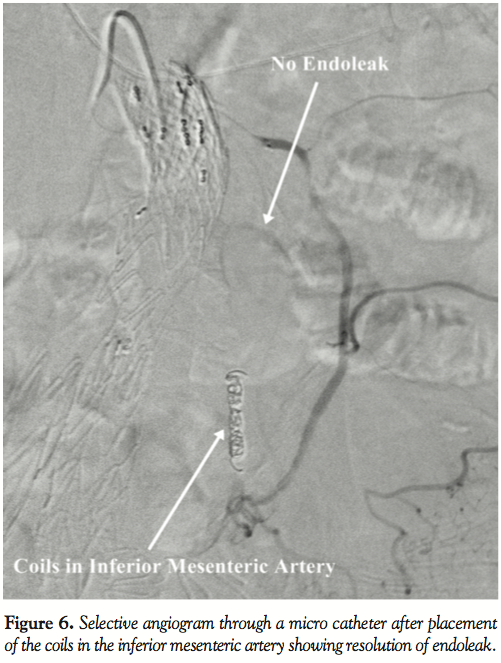

A few months later, CT scan was repeated and revealed a type 2 endoleak without enlargement of the sac; however, there was no reduction in the size of the sac (Figure 2). Multiplanar reconstruction was used and a small branch connecting the superior mesenteric artery (SMA) to the inferior mesenteric artery (IMA) through the marginal artery was found (Figure 3). Repeat angiogram confirmed that IMA was the source of the endoleak (Figure 4 and Video 3). Selective angiogram of the SMA was also performed, which showed filling of the aneurysm sac via the IMA (Figure 5 and Video 4). A microcatheter was advanced through the SMA and marginal artery into the IMA. The IMA was successfully occluded with coil embolization that resulted in complete resolution of the endoleak (Figure 6).